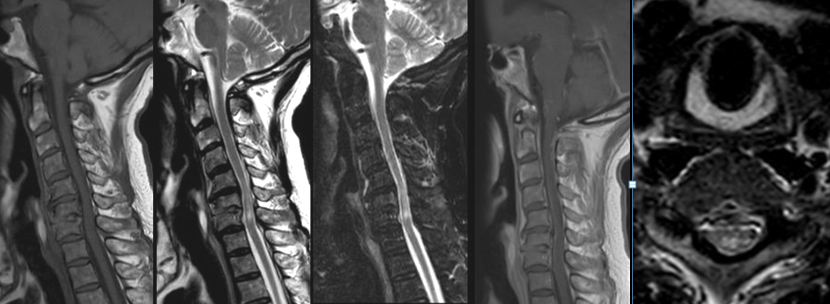

病例2

患者女性,41岁,间歇性双下肢无力2月,小便费力1月。

答案:脊髓硬脊膜动静脉瘘(SDAVF)。SDAVF是最常见的脊髓血管畸形,多累及胸腰段,占脊髓血管畸形的70%。本病中老年男性多见,多缓慢起病,并进行性加重,少数呈急性起病,临床确诊较难。临床表现步态异常、下肢乏力、感觉障碍、疼痛,伴或不伴括约肌功能障碍等。症状不典型时可误诊为周围神经病等,如表现为单侧下肢无力。表现为双足袜套样感觉异常时会误诊为糖尿病周围神经病等。表现为下肢放射性疼痛时被误诊为退行性脊椎疾病。脊髓MRI:T1示肿胀的脊髓呈低信号影,伴有弥漫性增强; T2呈多节段脊髓中央部高信号(大白萝卜样);脊髓背侧多有环状低信号(提示扩张、扭曲的静脉血管,呈小黑芝麻样)。

病例3

患者81岁,男。 突发腰背部疼痛伴排尿困难18d、双下肢麻木无力1d。

答案:脊髓血管畸形-硬脊膜动静脉瘘。解析同上。

病例4

患者70岁,男性,患者在急诊科就诊时出现菌血症症状。脑脊液分析显示蛋白质水平升高,淋巴细胞增多。

答案:脊髓梅毒。矢状位T2和STIR图像高信号,累及C5-C6节段颈髓后索。增强扫描未见病灶强化,也未见出血灶。轻微的软脑膜强化遍及脊髓前后表面。轴位T2图像显示脊髓后柱两侧对称性高信号。后柱病变是神经梅毒的晚期表现,导致脊髓后柱脱髓鞘。T2-STIR图像最常见的表现为对称性高信号和双侧高信号。一般增强无强化。

需要考虑的主要鉴别诊断包括:多发性硬化症:一般不对称,程度轻微。横贯性脊髓炎:通常不局限于后柱。HIV空泡性脊髓病:需要HIV感染史。肿瘤:不局限于后柱,脊髓增粗,增强有强化。缺血:急性发作,DWI弥散受限。在脑脊液分析中,梅毒螺旋体特异性抗体阳性,无其他微生物感染依据。